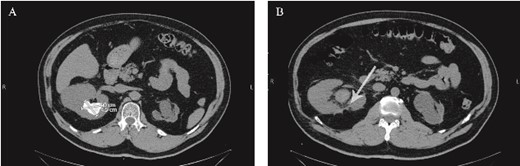

Eight days after discharge, he presented to the ED complaining of gross massive hematuria. He went into cardiac arrest, and cardiopulmonary resuscitation (CPR) was performed. His hemoglobin had dropped from 11.9 on the day of previous discharge to 6.8. He was later stabilized and started on blood transfusion and was put under close observation until he became hemodynamically stable. He underwent emergent renal arteriography, which showed RAP, and selective angioembolization was done (Fig. 2). Hematuria subsided after 2 days, and the patient was discharged. After 3 months, the patient was well and still in stage I CKD.

(A) Pseudoaneurysm seen on renal angiography. (B) The pseudoaneurysm following angioembolization.